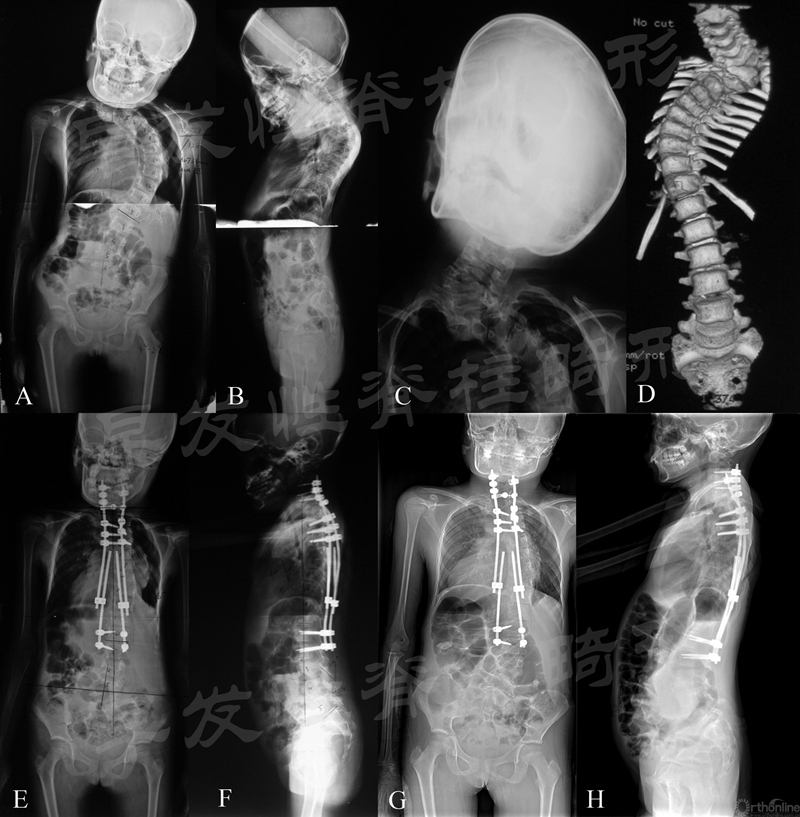

图4 患儿,女性,8岁。A~D.复杂颈胸段畸形伴胸椎严重侧凸;E、F.行颈胸段截骨短节段融合,远端使用双生长棒控制胸弯;G、H.术后3年提示矫形维持良好

图5 患儿,男性,6岁。A、B、G.严重先天性脊柱侧凸;C、D.行顶椎区截骨短节段融合以及双生长棒矫形;E~H.术后5年随访矫形满意,脊柱明显生长,胸廓发育良好

图6 患儿,女性,4岁。A~C、H.严重先天性脊柱侧凸;D、E.行顶椎区截骨短节段融合以及双生长棒矫形;F~I.术后3年随访矫形满意,脊柱明显生长,胸廓发育良好